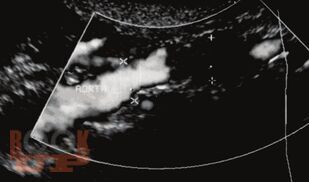

В учебном пособии дается обзор теоретических подходов, связанных с хирургической коррекцией окклюзионно-стенотических поражений в инфраингвинальном сегменте путем использования оптимального трансплантата для бедренно-подколенного шунтирования; представлены виды трансплантатов и их использование в хирургической практике.